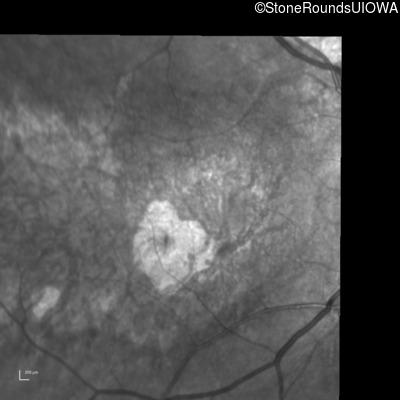

Infrared Fundus Photograph - Right - 20/100 +1 sc

Exemplar

Infrared Fundus Photograph - Left - 20/80 +1 sc